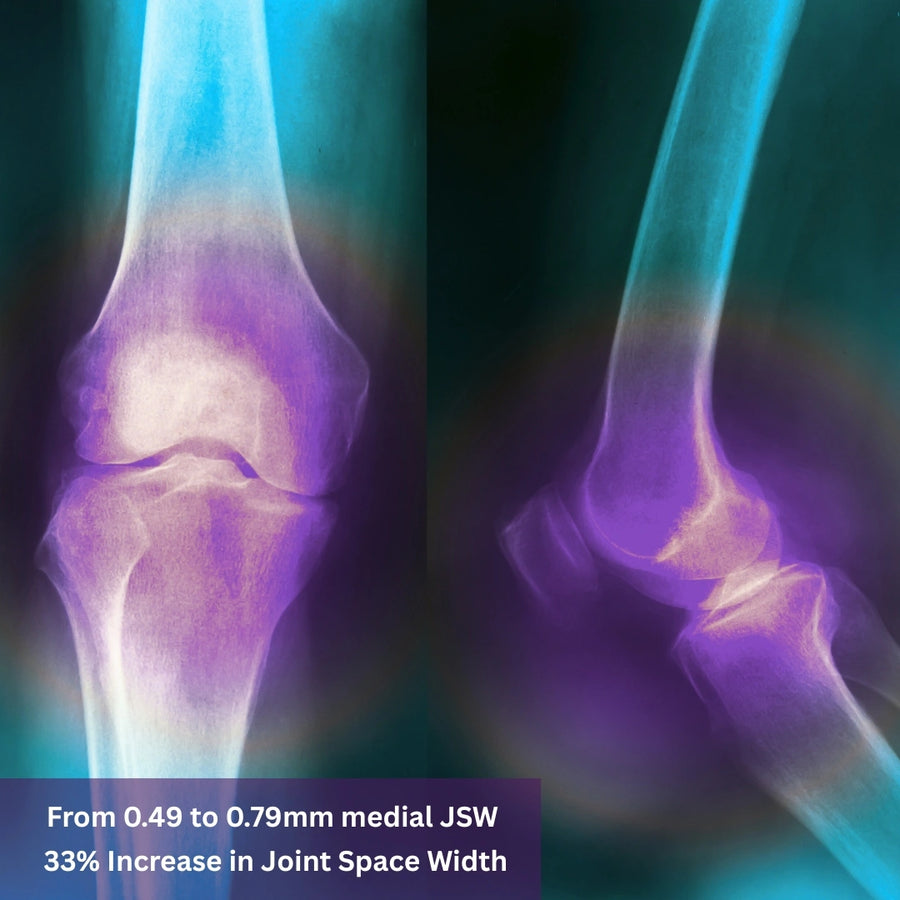

URAH’s patented MD-TECH transdermal delivery system has been made available to independent researchers around the world. That means scientists with no affiliation to URAH have tested and validated its formulations in real-world clinical settings.

URAH’s MD‑TECH has been featured in clinical studies published in internationally recognized pharmaceutical journals—strengthening its reputation as an effective solution for joint and bone care.